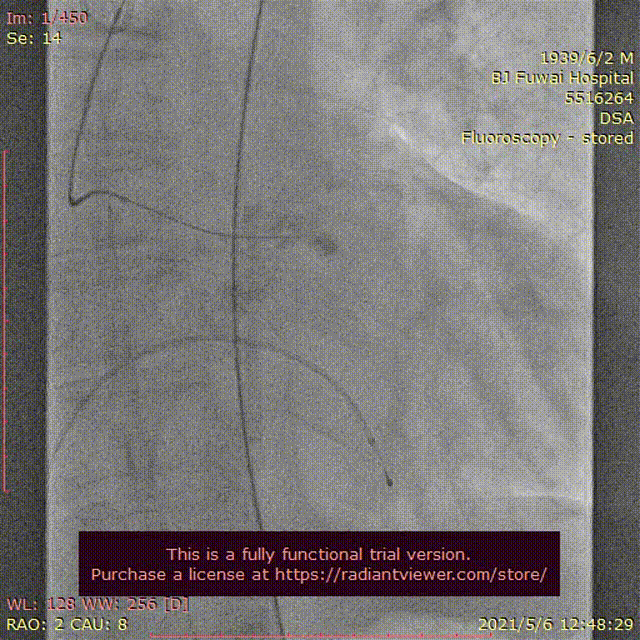

图3患者经导管主动脉瓣置换术及围术期操作

A:主动脉根部造影;B:23 mm球囊预扩张;C:26型号VenusA瓣膜植入;D:26型号VenusA“瓣中瓣”位置良好,少量瓣周漏;E和F:术前及术后经导管跨瓣压差;G:肘正中静脉留置针;H:患者全程清醒状态。